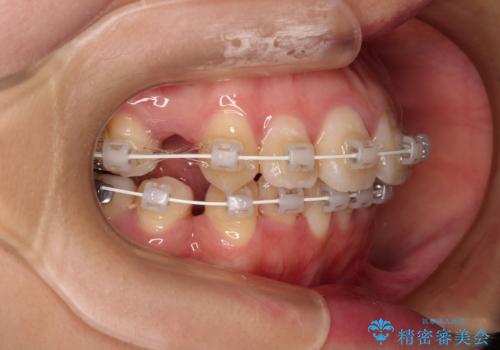

- 審美装置

突出感の強い上顎前歯をしっかりと後方移動させるため、上顎の裏側の補助装置(リンガルアーチ)とアンカースクリューを併用しています。

上下左右の第一小臼歯を抜歯して、目立ちにくいワイヤー装置で矯正を行いました。